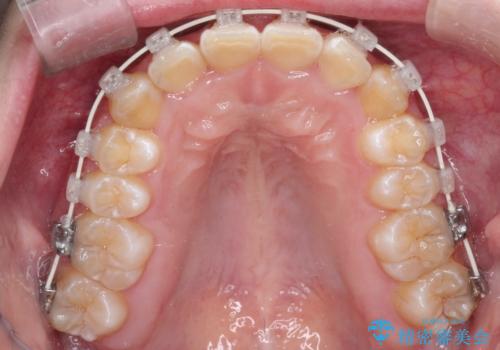

- 審美装置

- 1年6ヶ月

- 10-30回

ワイヤー矯正にて下顎前歯の圧下と臼歯部の挺出を効率的に行うことができました。